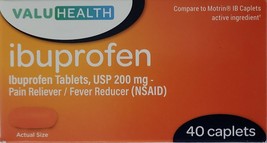

Category "Pain & Fever Relief"